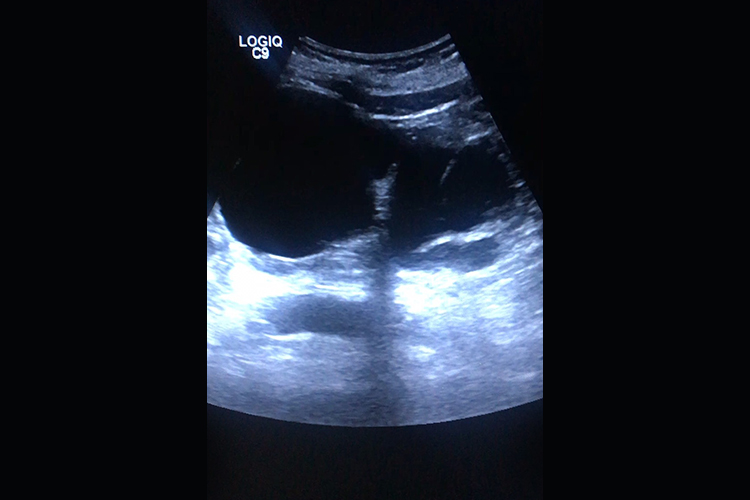

重度肾积水:重度肾积水肾体积增大,形态失常,肾盂、肾盏明显扩大,肾窦回声被调色板样或巨大囊肿样的无回声区所取代,肾实质厚度明显变薄,肾实质内彩色血流明显减少或消失,同侧输尿管扩张并与肾盂相连,输尿管也可不扩张。